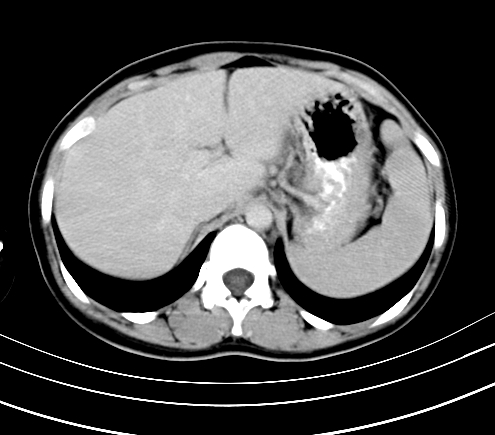

标题: CT23915:女 20岁 全身长疙瘩三年 今日多体位查 看看吧 [打印本页]

标题: CT23915:女 20岁 全身长疙瘩三年 今日多体位查 看看吧

腹部平扫

神经纤维瘤病

支持神经纤维瘤。